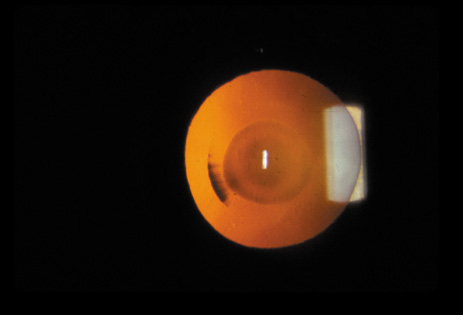

Nuclear cataracts tend to progress slowly. The refractive index of the lens changes as the nucleus progressively hardens, which usually results in increasing myopia.20,21 In some patients this is accompanied by optical distortion, especially of distant images, while near vision remains unaffected. A nuclear cataract is best seen with the narrow-beam direct illumination employed by the slit-lamp, which reveals the color and generalized haze or opalescence of the nucleus. In the early stages, the two halves (cotyledons) of the embryonic nucleus remain visible (Fig. 3). Later the entire nucleus appears as a homogeneous mass in contrast to the cortex (Fig. 4). Retroillumination may show the “oil droplet” effect (Fig. 5). Sometimes one may notice crystals in the lens nucleus (known as a Christmas tree cataract; Fig. 6A and B).

Fig. 5. “Oil droplet” appearance of a pure nuclear cataract seen on retroillumination examination.